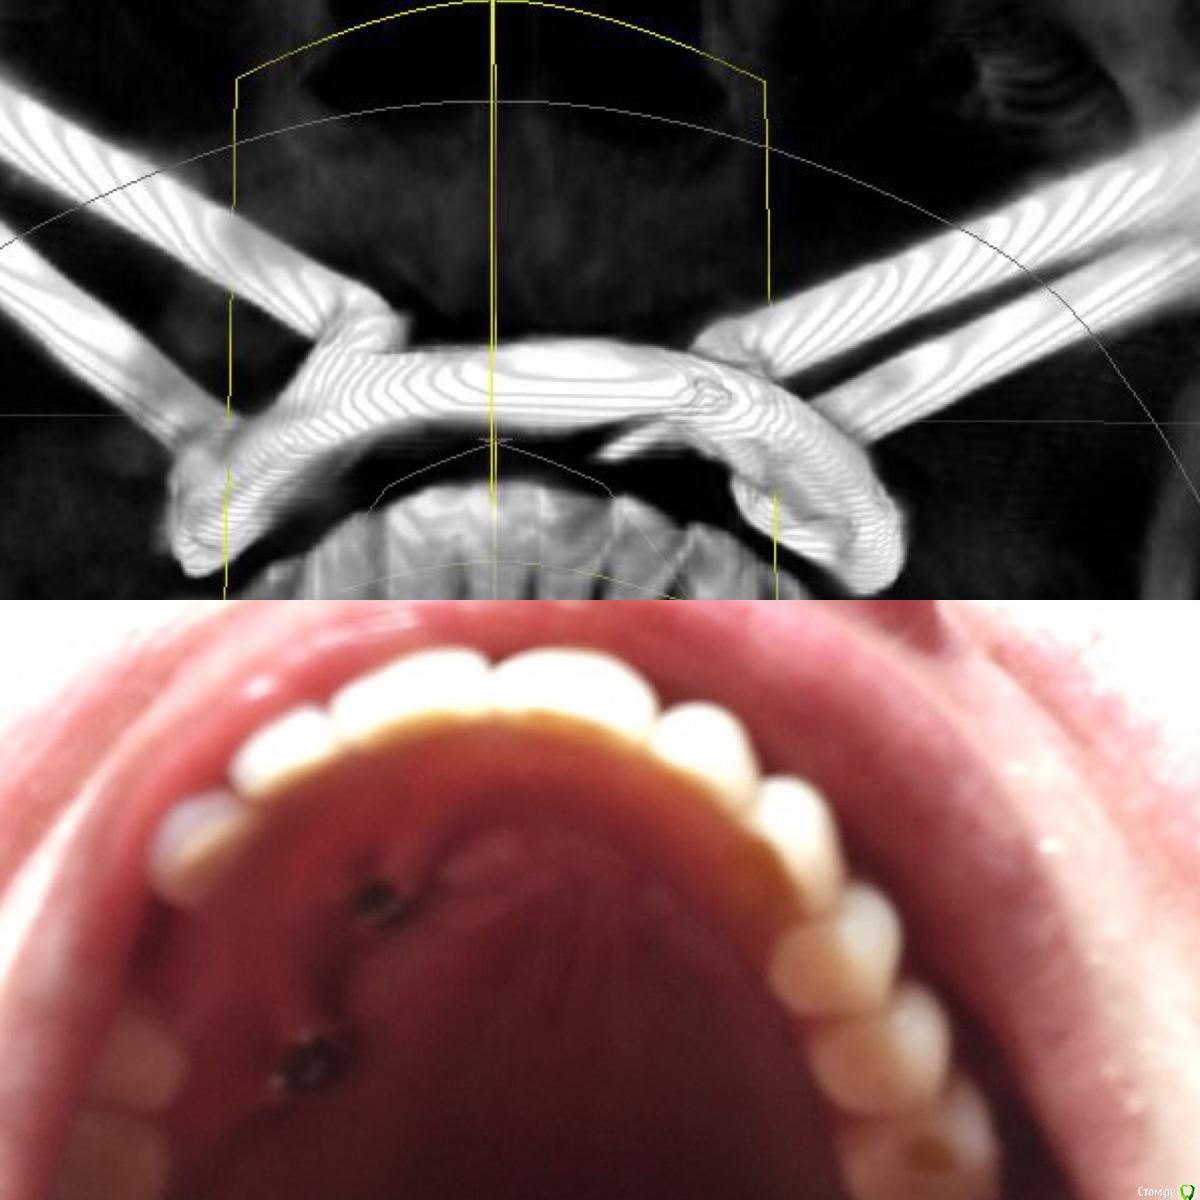

Maggie78rus Опубликовано 20 марта, 2017 Автор Поделиться Опубликовано 20 марта, 2017 (изменено) https://drive.google.com/open?id=0B5M5deCMkPdRdExpV1RRdTRGZ3MВот, присоединила некоторые фотографии. Прошу извинить за демонстрируемый кошмар, поверьте, мне ещё и больно плюс я не могу держать равновесие Разыскиваю хорошего ортопеда в Санкт-Петербурге. Слышала много вариантов лечения вплоть до ортогнатологической операции и переделки конструкции заново на других имплантатах. Изменено 20 марта, 2017 пользователем Maggie78rus Ссылка на комментарий

Maggie78rus Опубликовано 20 марта, 2017 Автор Поделиться Опубликовано 20 марта, 2017 ортопед это и есть "протезист" Ортодонт вам не нужен. Зубов то нет. Честно говоря данных мало. Почему надо ставить зигомы не ясно.Мне тоже не совсем ясно, зачем мне удалили одни имплантаты и поставили на другие протез с такой же окклюзией. Все, конечно, путается в голове от этого нескончаемого кошмара и , извините, зубной боли, хотя зубов уже 2 года нет- потеряла после первого протезирования. Очень устала.Проблему с окклюзией, я получила 8 лет назад.Тогда я ничего не могла сделать, не могу сделать ничего и сейчас. Какое-то дежавю: милые стоматологи встречают меня с распростертыми объятиями, берут деньги, потом у них ничего не получается, т.к. все снимали анатомические слепки и по ним отливали мосты, а теперь протез... Никто не пользовался артикулятором и лицевой дугой. Я приходила к врачам, надеясь получить качественную стоматологическую помощь. Для установки скуловых имплантатов мне даже обещали использовать высокие шведские технологии трёхмерного моделирования... но, погрузив меня в медикаментозный сон, опять сняли оттиск и отлили протез по образу и подобию того, что я так стремилась исправить: страшного, маленького, заваленного то на один, то на другой бок.И так три раза. У меня отваливался то передний зуб, то клык...ничто не убеждало врача сделать дугу об'емнее...в конце-концов я настояла на диагностике у гнатолога, но диагностические модели разбили в окклюдаторе.В Клинике все врачи -специалисты широкого профиля да ещё и лекции читают, но мне-то они помочь не могут и не хотят: они уже получили все деньги, извините, обманом, а у меня ещё не стоит временный протез с нормальной окклюзией.Что делать? Ума не приложу! То, что зубов нет и ты не чувствуешь, как идёт нагрузка от зубов, думаю, неправда. Чувствуешь. Чувствуешь, как нёбный шов уходит в сторону...Попросила собрать консилиум врачей, чтобы помочь советами - результат один- делают оттиск, потом делают вид, что моделируют на воске, иногда получается здорово! Но потом ставят все тот же оттиск, но под другим углом Ссылка на комментарий

Maggie78rus Опубликовано 20 марта, 2017 Автор Поделиться Опубликовано 20 марта, 2017 У меня центр верхней и нижней челюстей не совпадают. Не знаю было так или нет. Потом у меня небо не плоское и деформированное от неправильной нагрузки на мосты , а теперь его протез на зигомах дожимает, больно Ссылка на комментарий